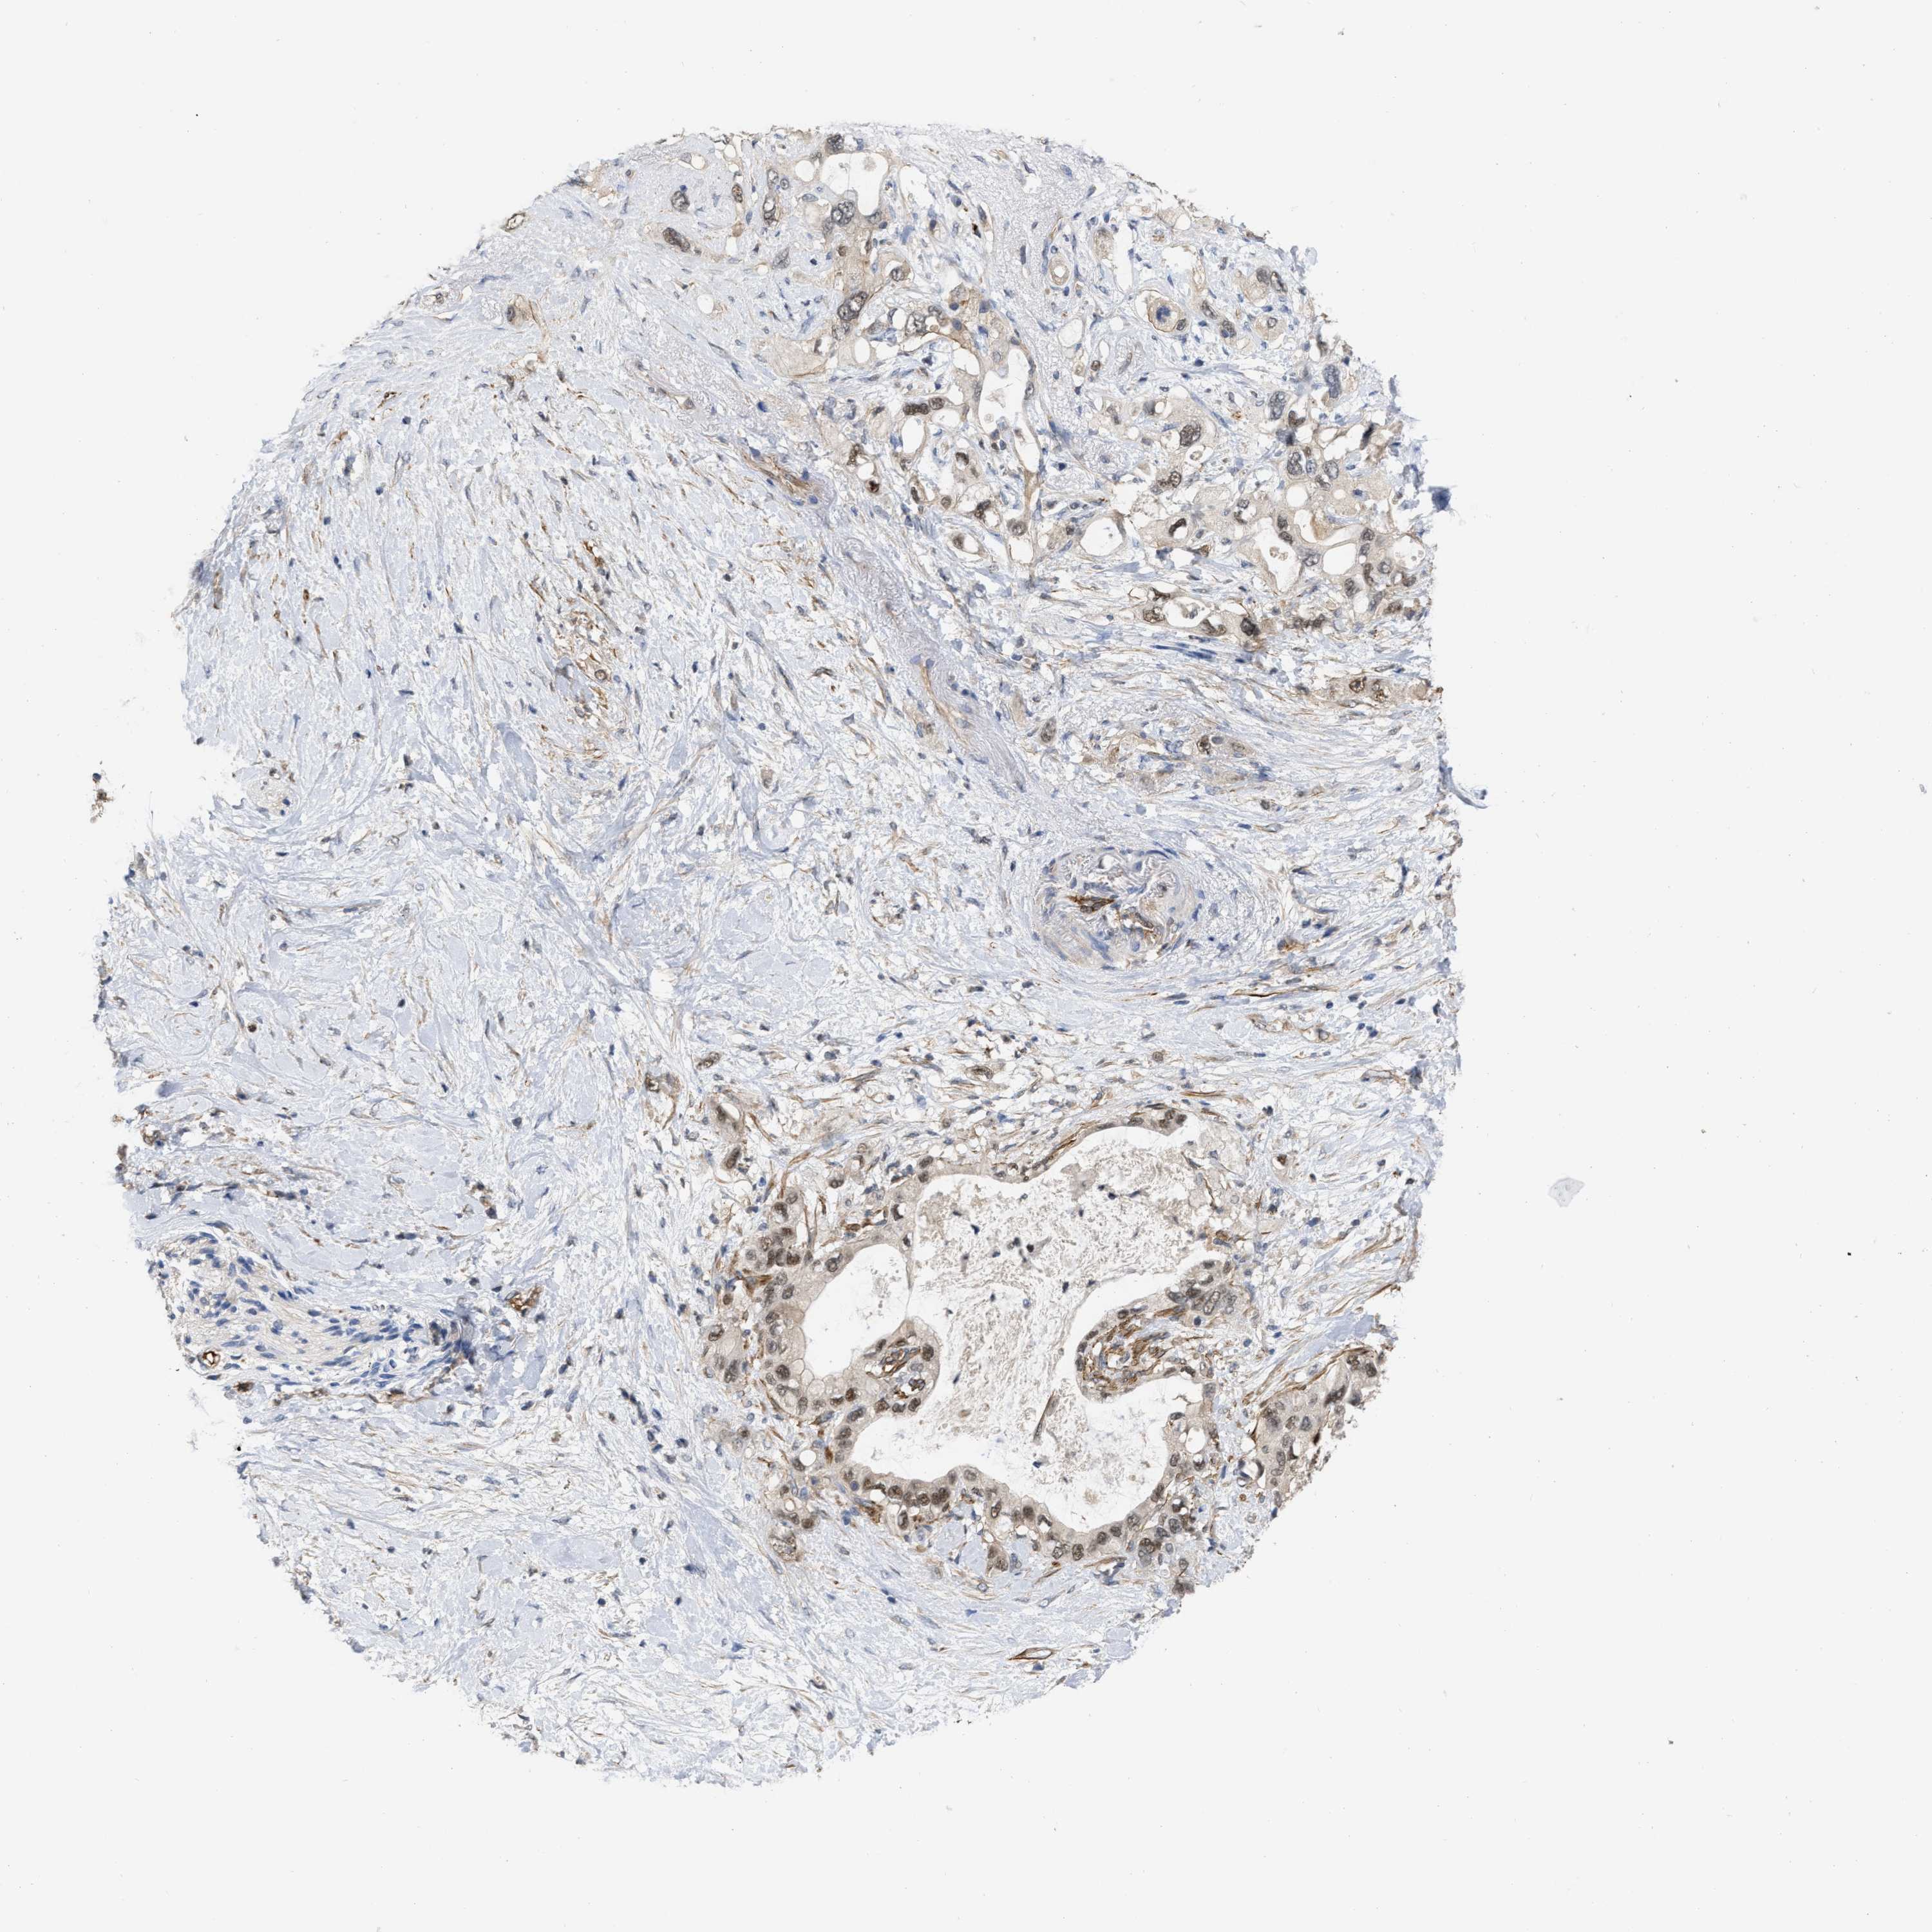

PANCREATIC CANCER - Protein expressioni

A mouse-over function shows sample information and annotation data. Click on an image to view it in a full screen mode. Samples can be filtered based on level of antibody staining by selecting one or several of the following categories: high, medium, low and not detected. The assay and annotation is described here.

Note that samples used for immunohistochemistry by the Human Protein Atlas do not correspond to samples in the TCGA dataset.

Antibody stainingi

Antibody staining in the annotated cell types in the current human tissue is reported as not detected, low, medium, or high, based on conventional immunohistochemistry profiling in selected tissues. This score is based on the combination of the staining intensity and fraction of stained cells.

Each image is clickable and will lead to virtual microscopy that enables deeper exploration of all samples and also displays staining intensity scores, fraction scores and subcellular localization as well as patient and tissue information for each sample.

Antibody HPA019832

Antibody HPA024338

Staining

High

Medium

Low

Not detected

Intensity

Strong

Moderate

Weak

Negative

Quantity

>75%

75%-25%

<25%

None

Location

Nuclear

Cytoplasmic/membranous

Cytoplasmic/membranous,nuclear

Adenocarcinoma, NOS